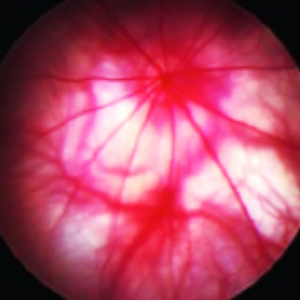

Ocular Assessments

CBI provides special techniques including, OCT (See our OCT video), ERG, ocular ultrasound, gonioscopy, tonometry, laser photocoagulation, slit lamp, funduscopy, pachymetry, Schirmer test, phenol red thread test, hypoxic or hyperoxic chambers, retinal angiography, device implantation, lens removal or insertion, whole mount preparation, ocular histology and immunohistochemistry and ocular photography.

- Funduscopy and Angiography

Histology Images